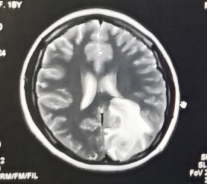

治疗后高颅压缓解,脑室恢复正常